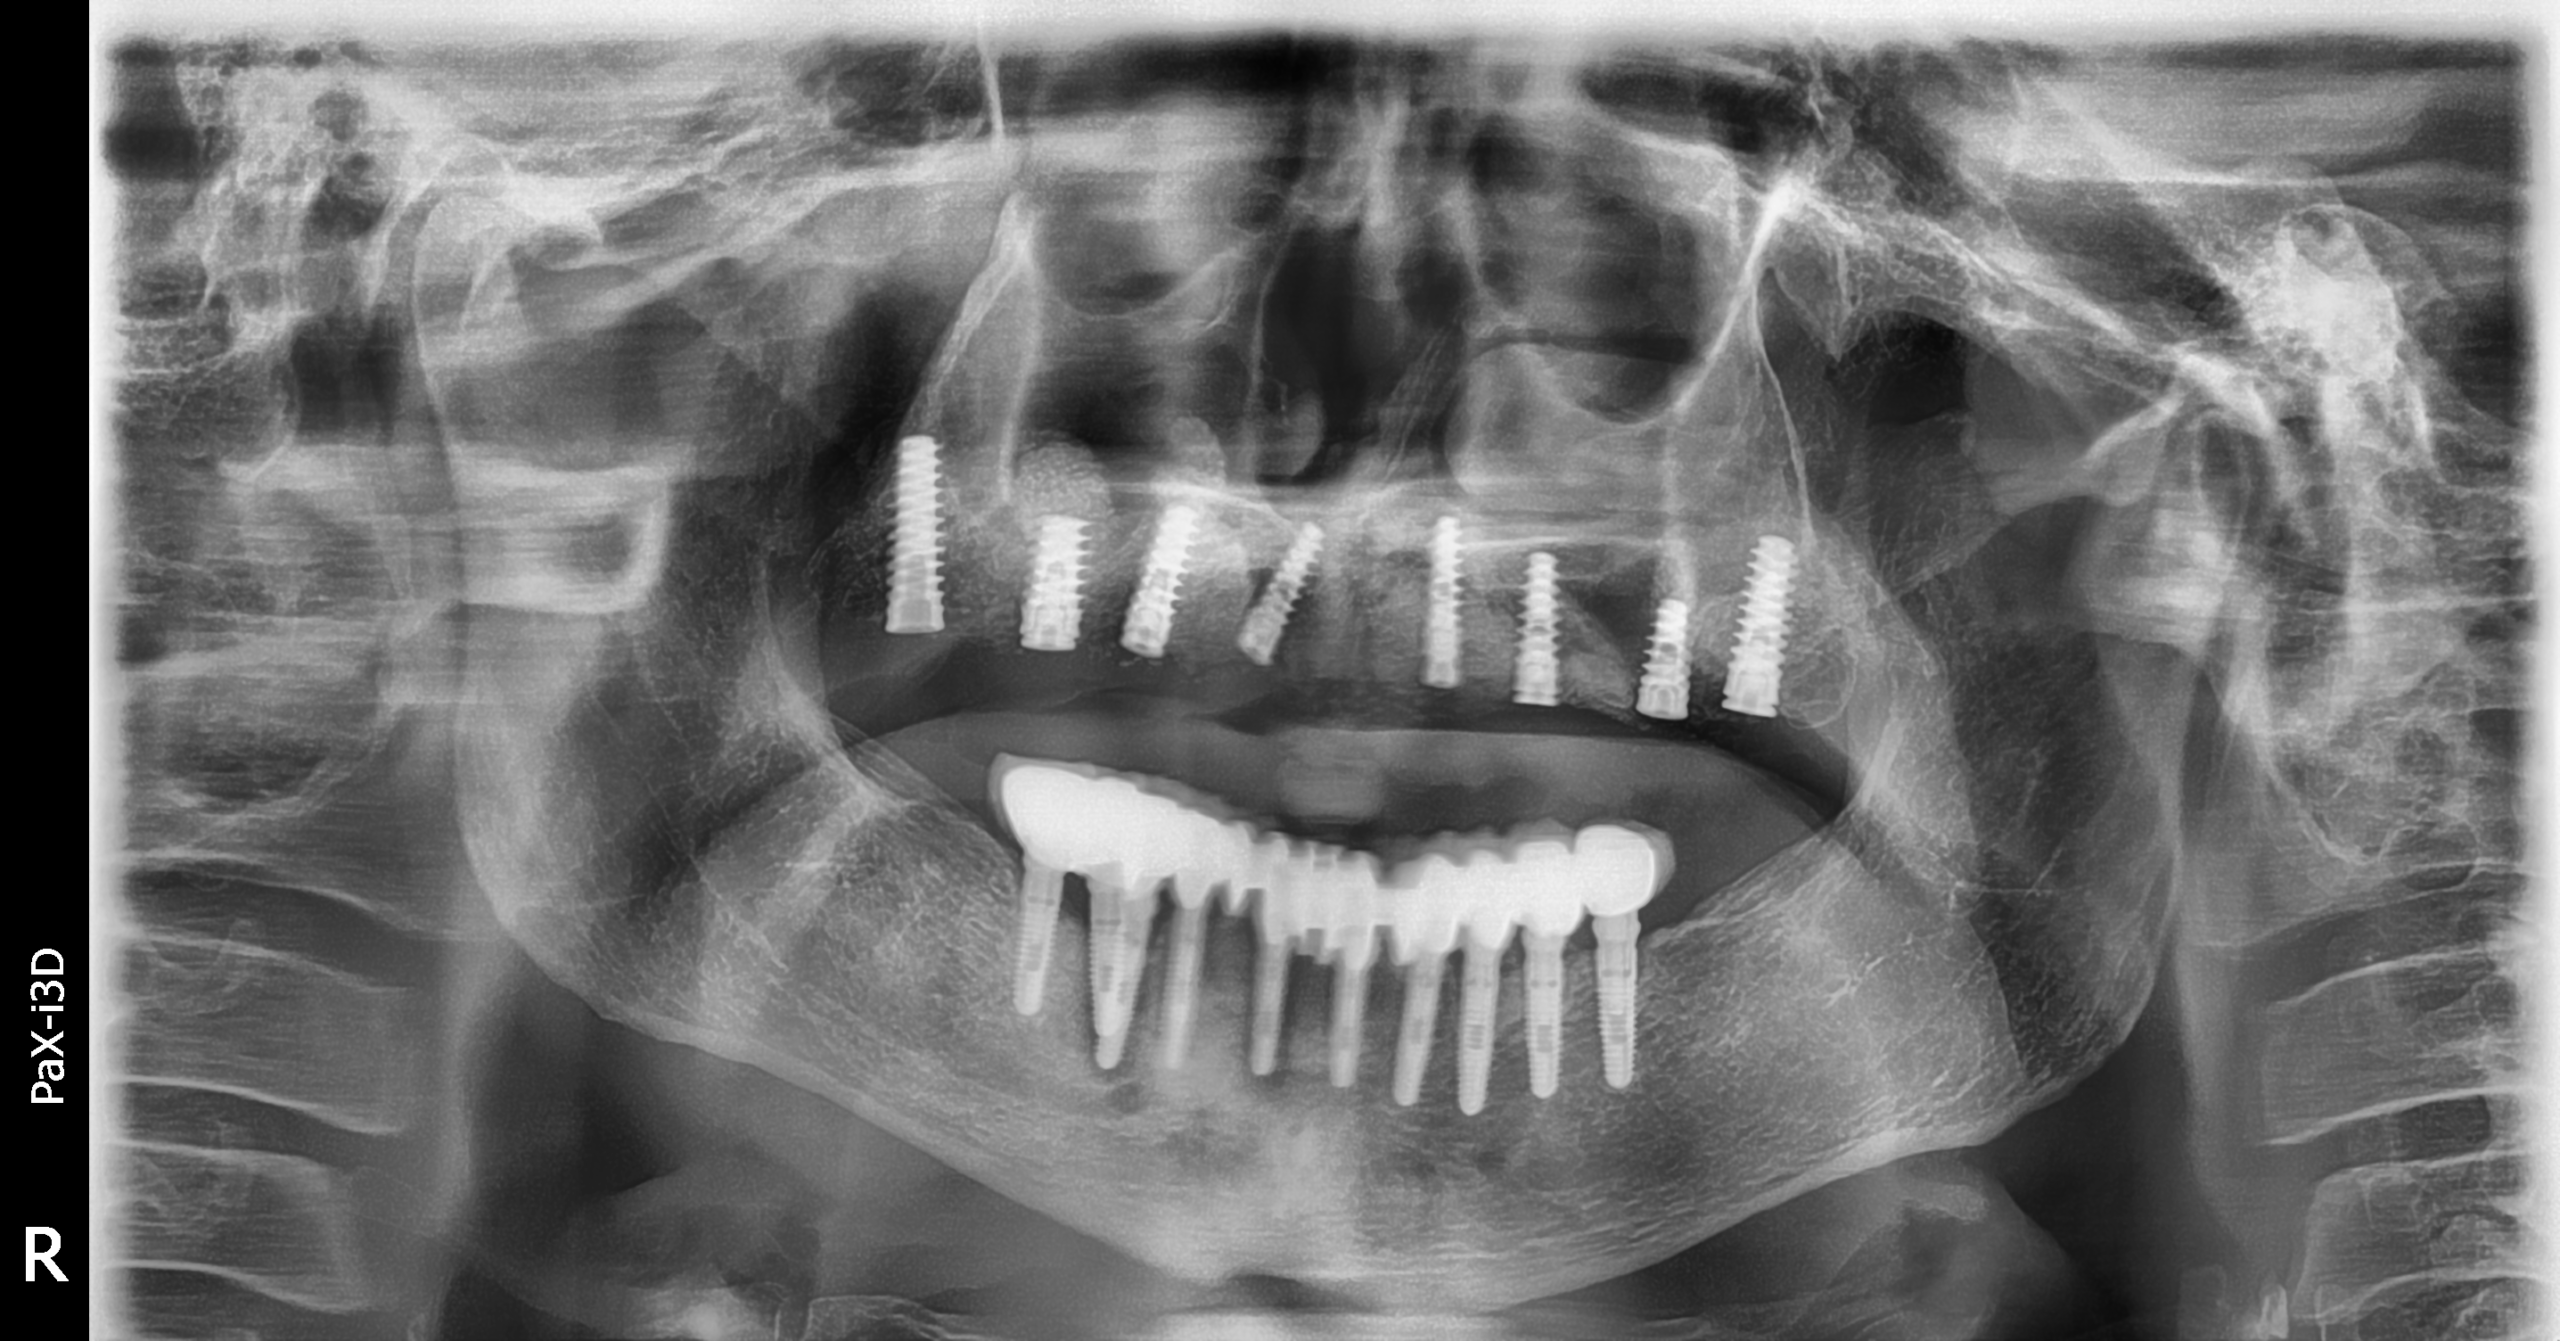

Implantes PHIA

Secuencia de imágenes RX, antes y después de la inserción de implantes PHIA en la parte superior de la boca.

Paciente varón de 82 años.

- Radiografía previa a la operación.

- Extracción implantes parte superior.

- Colocación implantes Radhex PHIA parte superior.